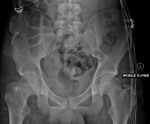

Malgaigne's fracture Joseph-François Malgaigne vertical pelvic fracture through both pubic rami and the ilium or sacroiliac joint with vertical displacement high energy impact to pelvis (front to back) Malgaigne's fracture Archived 2017-11-02 at the Wayback Machine at TheFreeDictionary.com